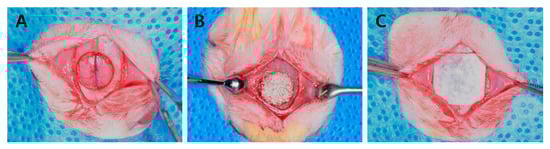

4.2.2. Surgical Procedures